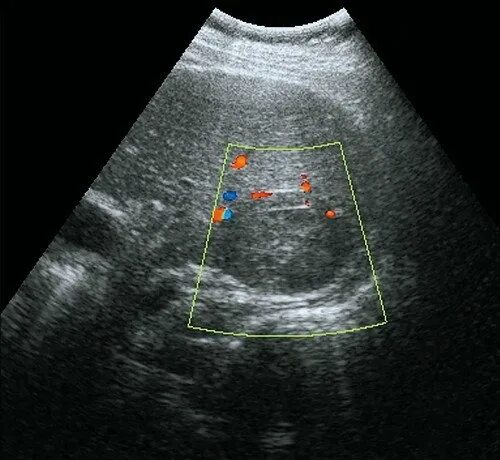

Метастазы в печени на узи